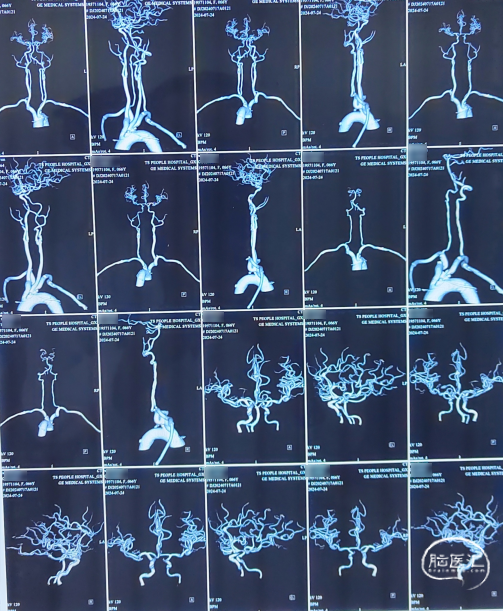

心脏彩超及甲状腺彩超。